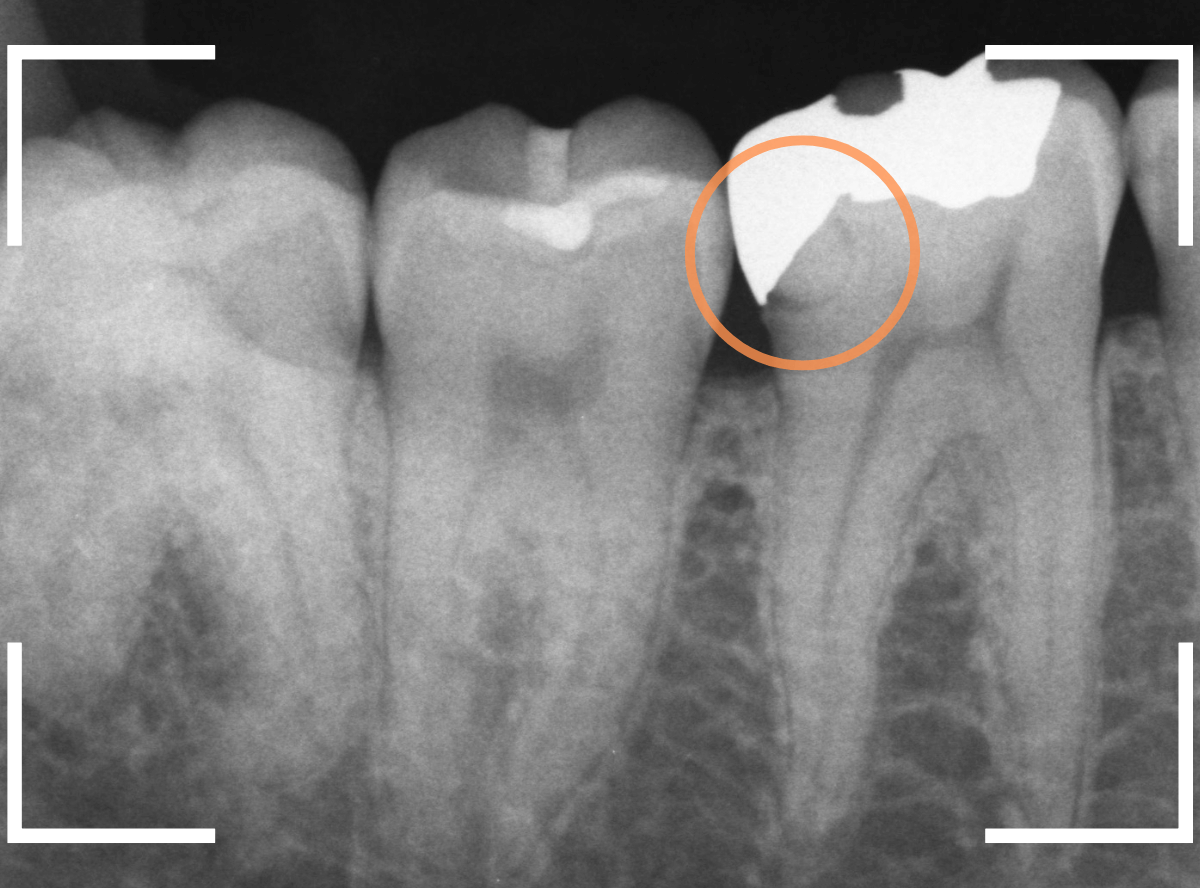

Case.12 検診で見つかった、インレーの下の深い虫歯

その中の一か所、上の奥歯のインレーの下の虫歯です。

見た目だけでははっきりわかりませんでしたが、レントゲン写真で確認すると、インレーの下で虫歯になっているのがわかります。

レントゲン写真で確認します。

赤い部分が虫歯と思われる部分、青い部分が歯の神経です。

確認すると、インレーの下まで虫歯が進行している可能性があります。